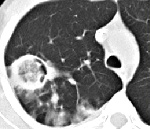

На рентгенограмме инвазивный аспергиллез обнаруживается поздно, поэтому рекомендуется компьютерная томография высокого разрешения. В течение первой недели заболевания при компьютерной томографии легких определяются несколько узлов с характерным венчиком (симптом ореола). Позже, в результате некроза инфильтрата, появляется область просветления в форме полумесяца (симптом мениска).